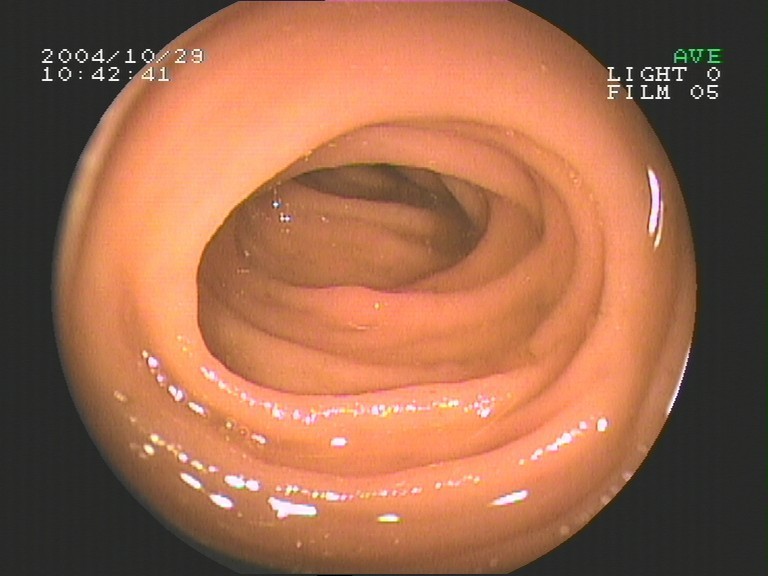

Coloskopie - Valvula Bauhini (Dünndarmklappe)